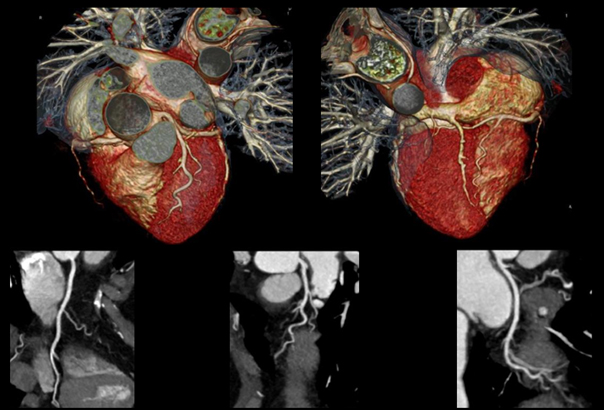

高端電腦斷層-心臟冠狀動脈掃描

影像醫學科主任/梁恒醫師

但自從多切面電腦斷層問世後,一切的侷限都改變了。電腦斷層成為冠狀動脈檢查的另一大利器。斷層掃描是利用 X光穿透人體後,利用電腦演算去呈現出二維及三維的影像。患者只需平躺置機器内,短短時間内即能獲得影像,快速方便而安全。

心臟冠狀動脈掃描

例如384 切表示探頭轉一圈可以得到 384 張切面圖像。數字越大,得到的圖像越多,重組後獲得的影像更為完整精確,而隨著切數增加,掃秒範圍的加大,偵測器旋轉的時間縮短。種種硬、軟體困難的克服,大幅減低了傳統電腦斷層的缺點,尤其是放射線劑量方面更為顯著。

隨著影像的顯現更為精準而明確,因此可以顯示更細的冠狀動脈分枝。心臟内科及影像醫學科醫師因此也能更精確的診斷冠狀動脈方面的疾病及變化。更能協助醫師們評估病患冠狀動脈堵塞與發生血管栓塞的危險程度,達到早期治療,以及預防心血管疾病發作的目標。尤其是有心臟病史、曾經中風的患者,此外,長期吸菸的瘾君子、具三高條件(血壓、血糖、血脂)等心血管容易出現問題高危險族群,以及懷疑自己有心血管疾病、有胸痛症狀的患者。

有鑑於此,本院即將特別引進更高端的電腦斷層儀器,其特點為:

• 更低的檢查放射線劑量 <平均5-6mSv最低可至 3mSv。

• 更高的影像解析度。

• 更小的心跳因素侷限。

• 更短的掃描時間。